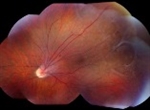

The patient presented with new worsening vision in both eyes. Around one month prior to presentation, he was switched to immunotherapy with ipilimumab, nivolumab, and cabozantinib. Visual acuity measured count fingers in both eyes from a previous 20/80 in the right eye (OD) and 20/200 in the left eye (OS). Intraocular pressure, pupillary exam, and confrontational visual fields were normal. Anterior segment examination was overall unremarkable with clear corneas and trace nuclear sclerotic cataracts bilaterally. Dilated fundoscopic exam showed new mild bilateral vitritis and stable bilateral choroidal lesions with overlying pigmentary changes (Figure 1). Greater subretinal fluid was present in the macula than previously observed. Optical coherence tomography confirmed increased subretinal fluid and revealed a subretinal fibrinoid response (Figure 2).

Figure 1. Color fundus photos showing bilateral choroidal lesions with overlying pigment changes. |